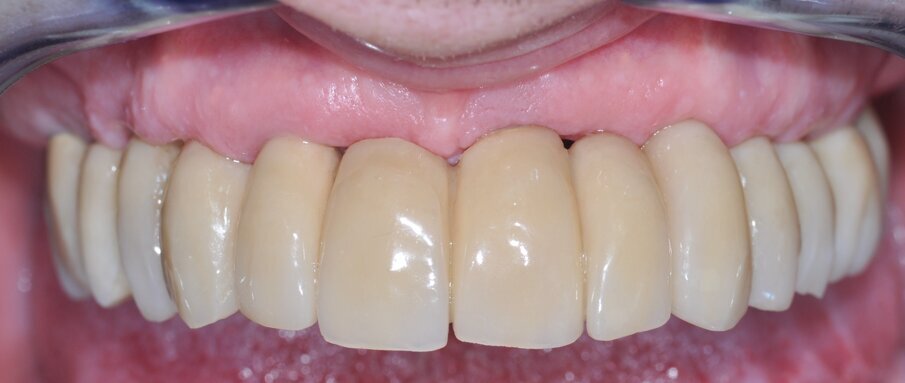

Un approccio flapless è stato usato in 11 casi e in 41 arcate è stata eseguita anche una procedura di rigenerazione (quasi nel 50% dei casi). I tessuti molli si mostravano in salute e liberi da segni o sintomi di mucosite al momento della rimozione della protesi provvisoria, così come all’ultimo follow-up nel 90% dei casi (Fig. 6). Il controllo radiologico ha dimostrato costantemente una sostanziale preservazione dell’osso marginale per l’intera coorte di pazienti (Fig. 7).

Fig. 6_Foto intra-orale a tre anni dall’intervento in cui si apprezza la salute e il buon mantenimento delle mucose.